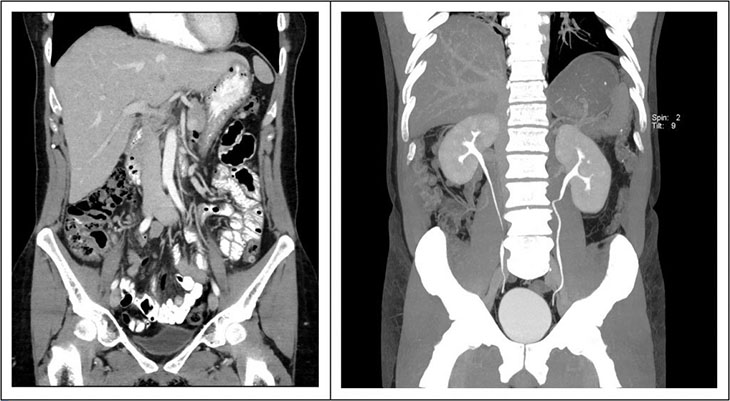

• Chụp cắt lớp vi tính (CT scan): Giúp xác định rõ ràng hơn về kích thước, số lượng và vị trí chính xác của sỏi thận.